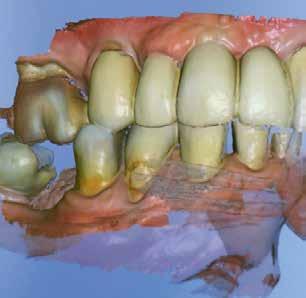

A laboratóriumban szekciós minta készült, blokk-stiftekkel (1. kép) , amelynek készítése során nagy figyelmet szenteltünk az ínymaszk (Majesthetik- Gingiimplant picodent) és a felfekvő lengőtag területének (2–6. képek)

A minta beolvasása után számítógéppel terveztük meg a híd vázát (7. kép). 0,06 mm-es cementrést terveztünk a teljes karfelület alá, 1 mmre végződve a preparáció szélétől (8–11. képek)